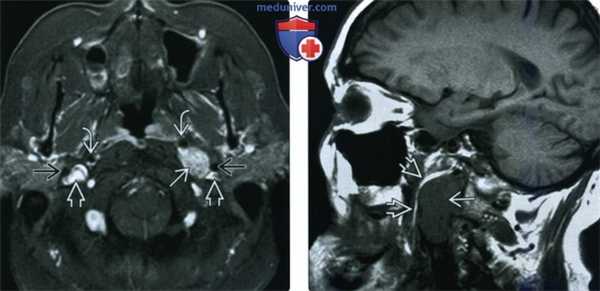

(Слева) МРТ Т1ВИ FS с КУ, достаточно небольшая опухоль блуждающего гломуса слева. Сравните положение внутренней сонной артерии, яремной вены и шиловидного отростка со здоровой и с пораженной сторон.

(Справа) МРТ Т1ВИ, сагиттальная проекция. Новообразование с четкими контурами и сигналом промежуточной интенсивности. Обратите внимание, что образование имеет извитую форму и расположено вдоль длинной оси сонного пространства. На сагиттальном срезе видно, что окологлоточная жировая клетчатка смещена вперед.